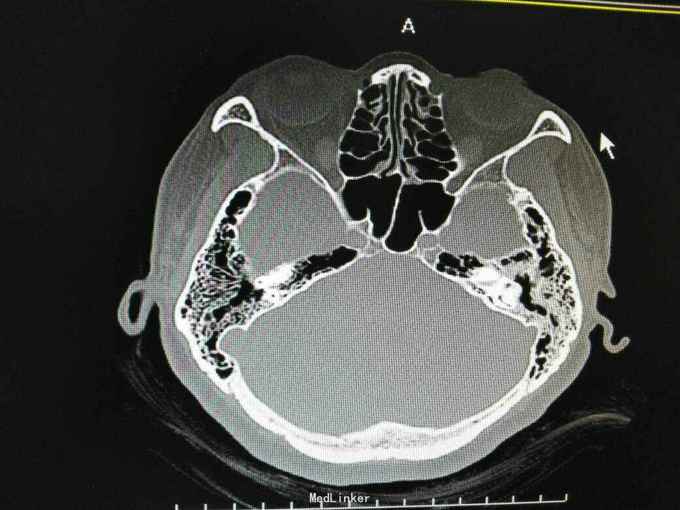

外耳道胆脂瘤,并 分泌性中耳炎? 胆固醇肉芽肿?

患者女性,47岁,以听力下降一周为主诉入院。 就诊后见外耳道后壁缺损,鼓室內积液,给予抗炎治疗后,鼓室內积液由缺损外耳道排出,呈棕褐色。 辅助检查:纯音听阈基本无听力损失。 诊断 外耳道胆脂瘤,并 分泌性中耳炎? 胆固醇肉芽肿? 治疗: 1.乳突根治术?乳突蜂房气化非常好,比较难做。 2.外耳道成型、后壁修补?